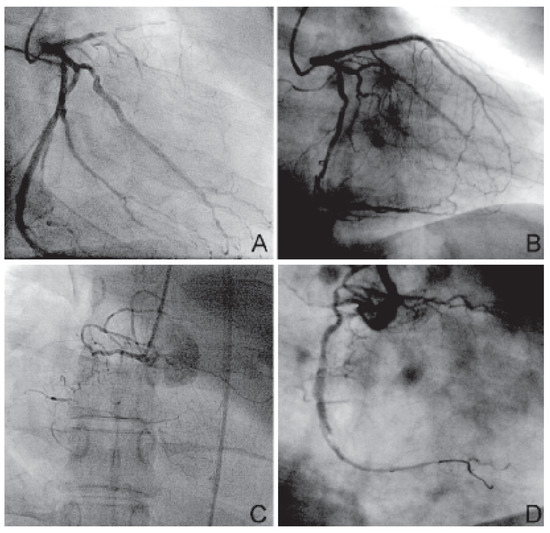

Koronarrevaskularisation ohne Herz-Lungen-Maschine bei Thrombozytopenischer Purpura (M. Werlhof)

We report a case of a 75-year-old male suffering from Werlhof ’s disease and coronary artery disease undergoing off-pump coronary artery bypass grafting (OPCAB). At the time of admission, platelet count was 24 × 103/μl. After four days of treatment with [...] Read more.

We report a case of a 75-year-old male suffering from Werlhof ’s disease and coronary artery disease undergoing off-pump coronary artery bypass grafting (OPCAB). At the time of admission, platelet count was 24 × 103/μl. After four days of treatment with Octagam® (Octapharma, Switzerland), an intravenous immune globulin, preoperative platelet count increasd to 80 × 103/μl. To prevent potential bleeding complications two units of thrombocytes were administered intraoperatively. Revascularisation was uneventful. The patient was discharged from ICU on post-operative day (POD) 1. Total chest drainage was 920 ml, requiring the transfusion of one red blood cell concentrate only. Further postoperative course was uneventful and the patient was discharged from hospital on POD 9. We conclude that in patients with Werlhof ’s disease OPCAB surgery can be safely performed. Full article

Show Figures

Figure 1